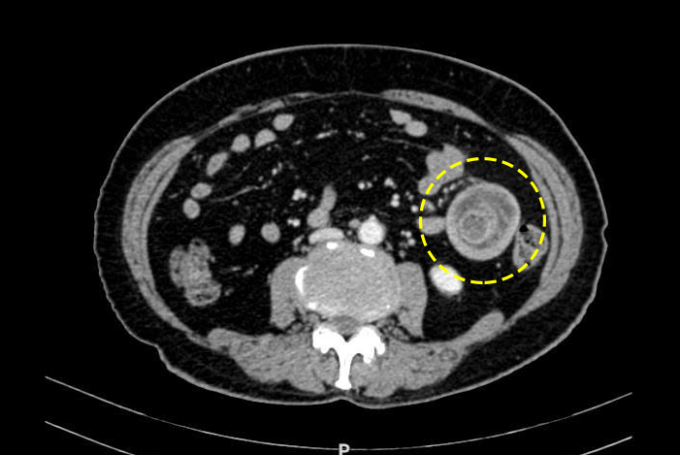

Bác sĩ có thể phát hiện lồng ruột khi khám lâm sàng. Siêu âm bụng có thể cho thấy lồng ruột nhưng độ nhạy kém hơn CT do bị ảnh hưởng bởi khí trong các quai ruột. CT cũng hỗ trợ xác định vị trí tắc nghẽn, đánh giá tình trạng mạch máu và định hướng xác định nguyên nhân gây lồng ruột.

Khối lồng ruột trên phim chụp CT. Ảnh: Bệnh viện Đa khoa Tâm Anh